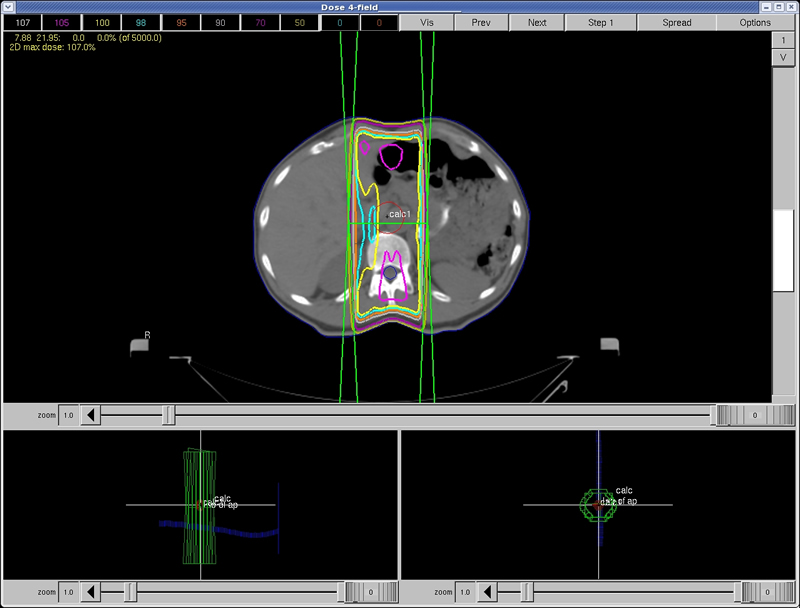

Quiz: Question 12

In this treatment plan, adding lateral beams will:

a) Increase the dose to the liver, and decrease the dose to the spinal cord b) Decrease the dose to the liver, and increase the dose to the spinal cord c) Decrease the dose to the liver, and decrease the dose to the spinal cord d) Increase the dose to the liver, and increase the dose to the spinal cord